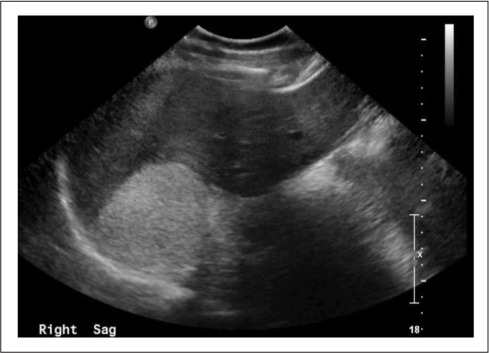

一名38岁男性,既往有2型糖尿病和血红蛋白SCD病史,于2014年在内分泌外科诊所接受初步评估。他在接受腹部超声检查时偶然发现右肾上腺肿块(图1)。患者无任何腹痛、体重增加或可归因于肿块效应的症状。他唯一的主诉是疲劳,他把这归因于他的SCD。此时,包括血浆后肾功能和低剂量地塞米松抑制试验在内的生化指标正常。

图1